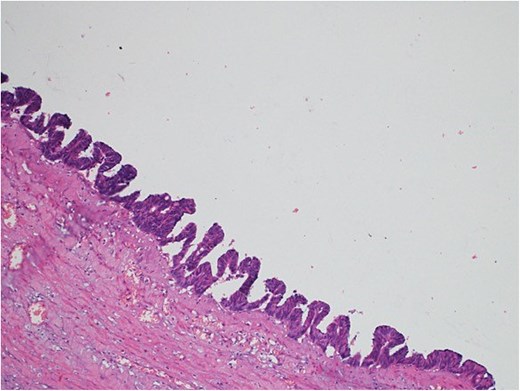

A 46-year-old male with a history of leukemia treated with chemotherapy and primary infertility presented with right lower quadrant abdominal pain of less than one day's duration. He reported associated nausea but no vomiting, changes in bowel habits, or fever. On systemic evaluation, the patient demonstrated stable vital signs, full consciousness, and alertness, with no evidence of severe pain. Abdominal examination revealed rebound tenderness in the RLQ, but the abdomen was otherwise soft, with no tenderness upon palpation of other regions. Laboratory investigations were within normal limits. Abdominal CT with contrast revealed evidence of appendiceal perforation. The liver showed moderate to severe steatosis, but no other remarkable abnormalities were detected (Fig. 5). Due to the perforation near the base of the appendix, a right hemicolectomy was performed. Histopathological examination of the appendix confirmed the diagnosis of LAMN (Fig. 6). The tumor extended to the visceral peritoneum through the perforation site, but there was no evidence of lymphatic, vascular, or perineural invasion. Four reactive lymph nodes were negative for tumor infiltration, and the pathologic TNM staging was pT4, pN0. The specimen also contained acellular mucin evacuated during the surgery. Postoperative recovery was uneventful, and the patient was later transferred to a higher center for comprehensive assessment and continued care.

Light microscopy images of the appendix (A, B) show low-grade dysplastic epithelium on the surface of the appendix (hematoxylin and eosin stain; 4×).